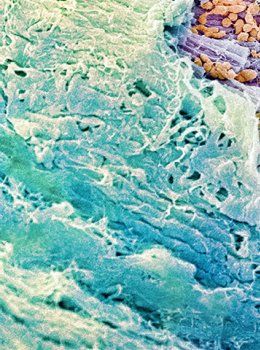

The Wonderful World of 3D+